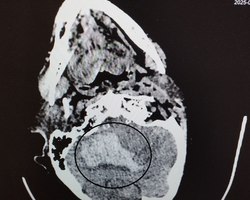

Обследовав женщину, врачи поставили диагноз – геморрагический инсульт правого полушария мозжечка, сопровождающийся внутримозговой гематомой, прорывом крови в желудочковую систему и кровоизлиянием.

На фото – томогораммы, на которых видны внутримозговые гематомы в области правого полушария мозжечка, в стволе головного мозга, кровоизлияния в желудочковую систему мозга.